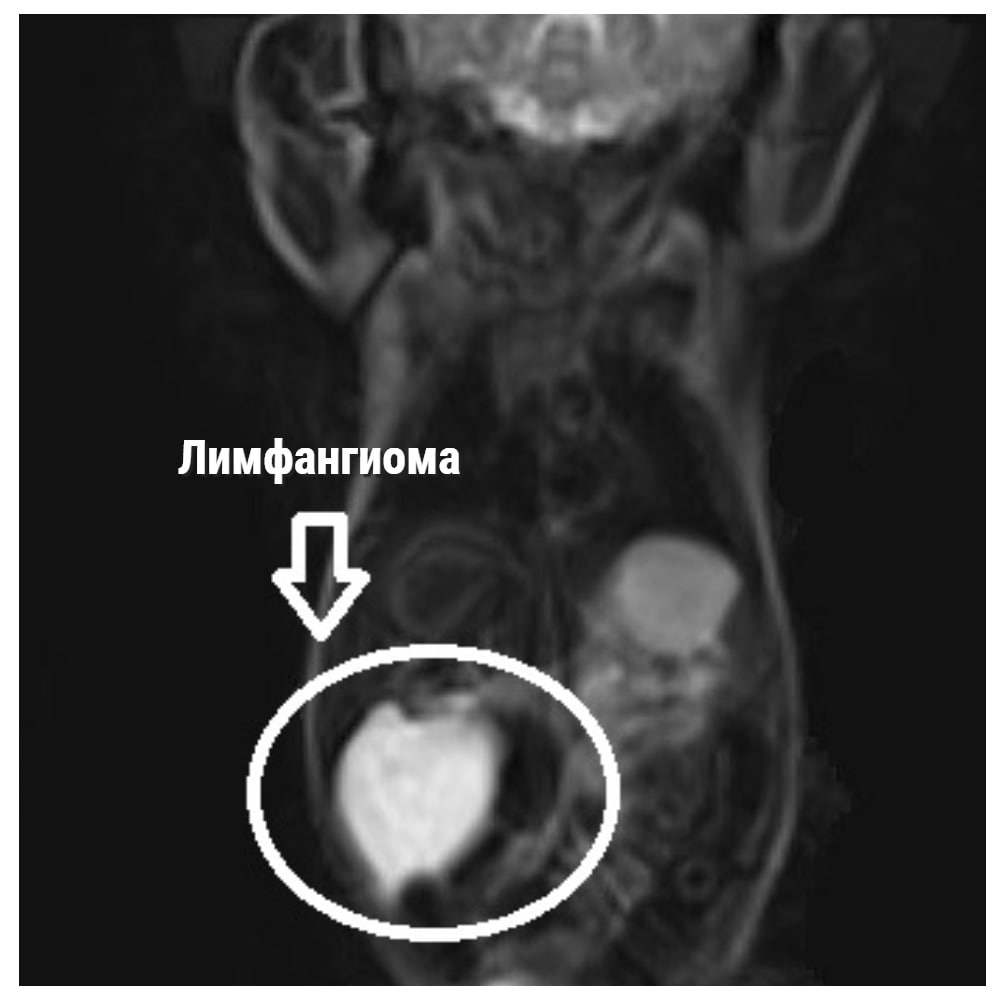

«После рождения состояние ребенка было стабильным, началось дообследование: УЗИ, МРТ. По данным УЗИ, в  проекции правой доли печени визуализировалось  образование неправильной округлой формы, с неровными, но достаточно четкими контурами, многокамерное, размером почти 6 на 3 см», - сказал заведующий отделением хирургии новорожденных Михаил Рехвиашвили.

«На 7 сутки жизни проведено радикальное хирургическое удаление образования. Было выявлено, что образование представлено одной кистой, сообщающейся с более мелкой кистой. Визуально образование соответствовало лимфангиоме печени – доброкачественному образованию, что подтвердили последующие исследования. Проведено радикальное удаление образования в пределах здоровых тканей. Операция проводилась полностью лапароскопически – через мини-проколы передней брюшной стенки. После операции разрезы практически не заметны», - добавил Рехвиашвили.